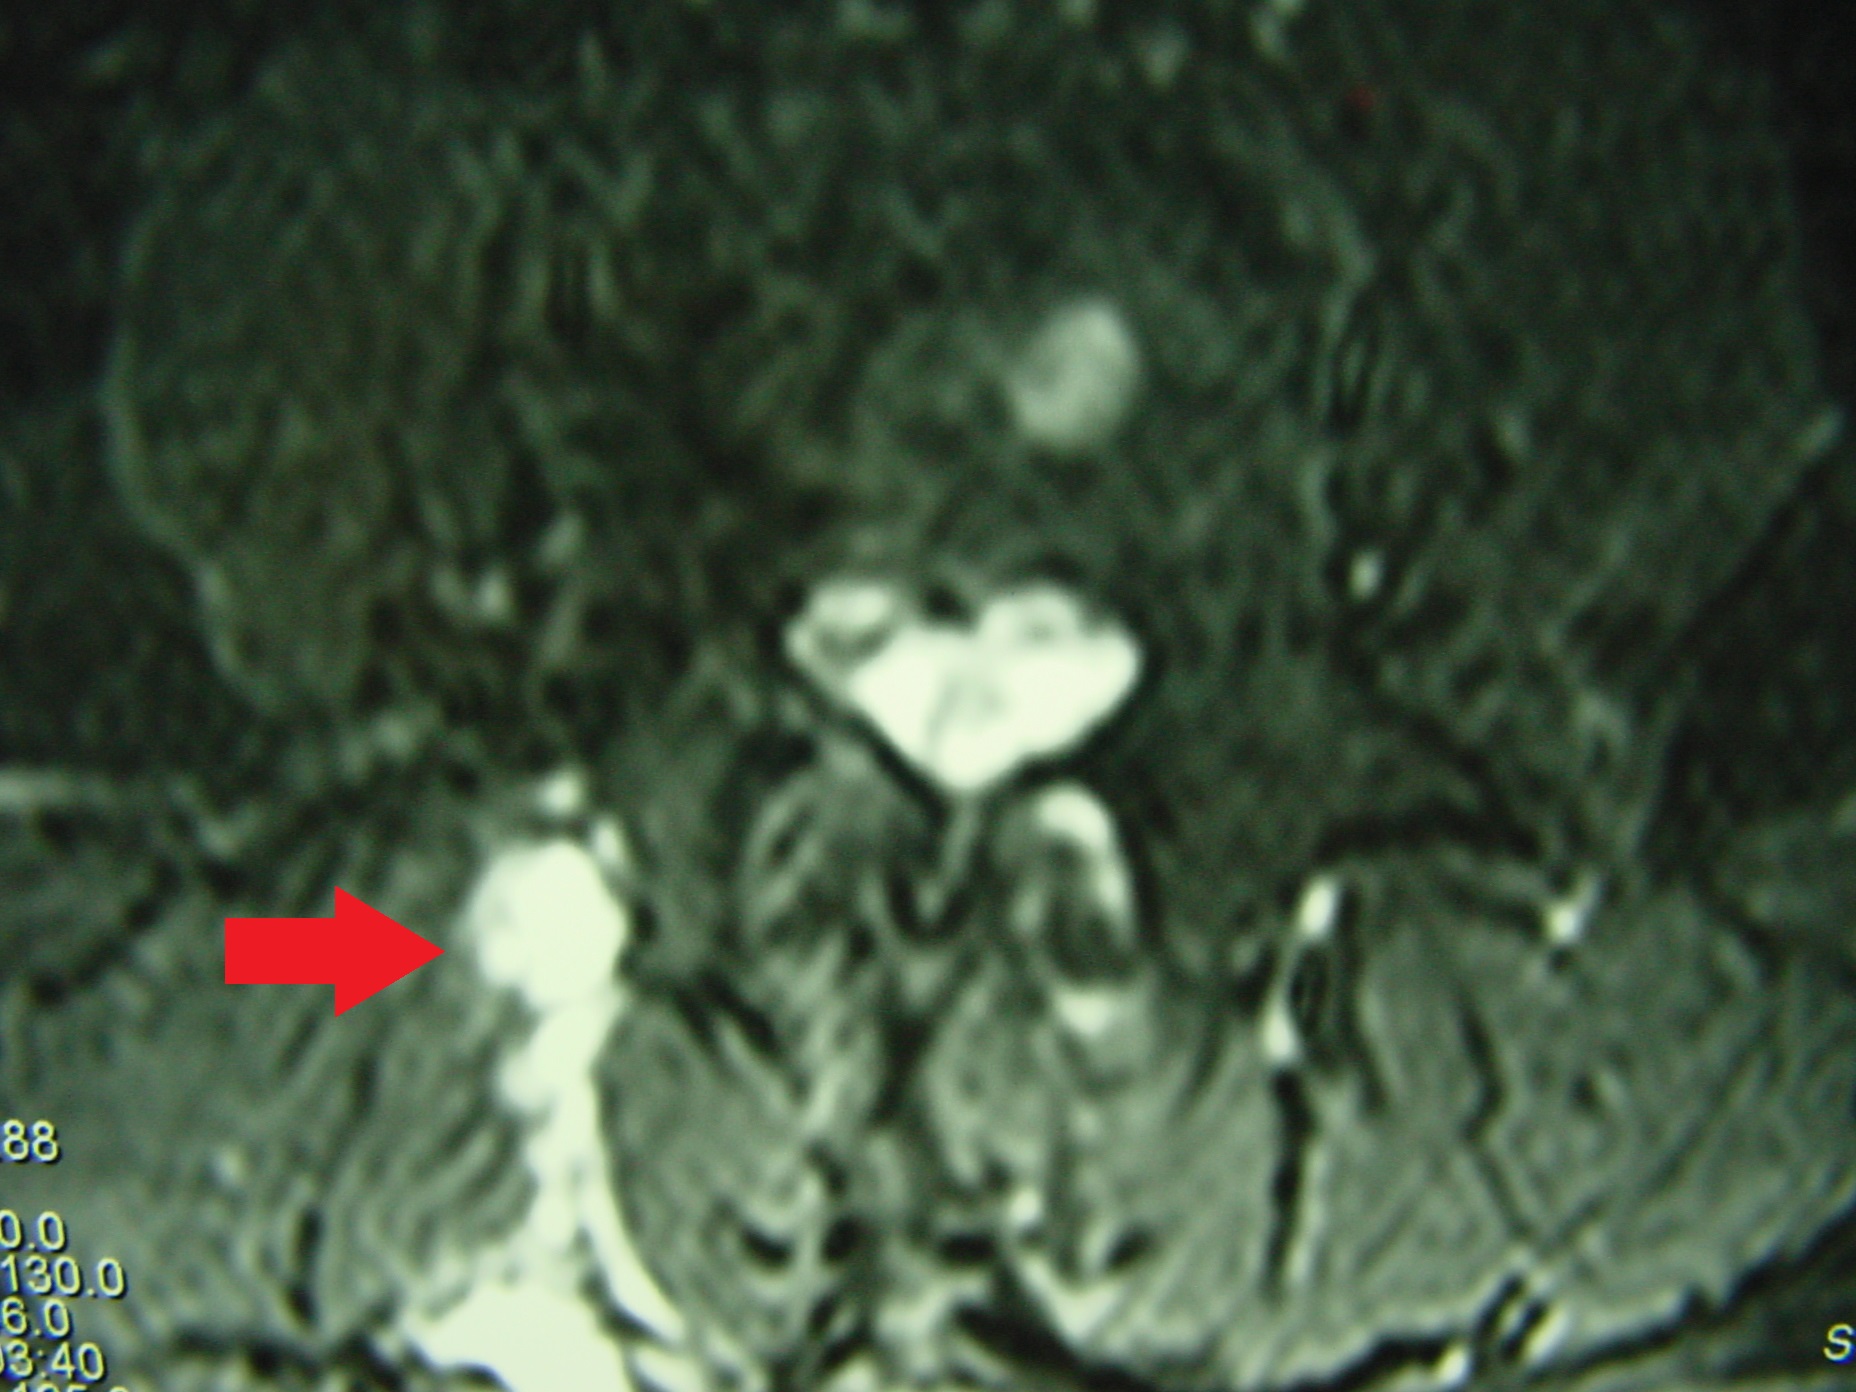

DSC00087_bakas_echinococos